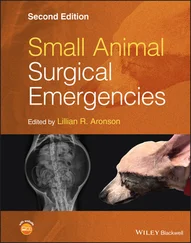

Figure 6.30. HRU view in a dog. In (A) and (B) the direction of the probe is shown externally ventral to midline at the level of the umbilicus with the objective to image and fan through the most gravity‐dependent “HRU pouch” illustrated by the white curved line. (B) A similar image with anatomy overlay that correlates with CT image in (C). The target organs for the HRU (and SRU) view are in reality the small intestine and spleen and either or both should be recognized to confirm that you are imaging the abdominal cavity. In (D), (E) and (F) the expected sonographic images are shown. Computed tomography courtesy of Dr Daniel Rodriguez, VETTEM, and Dr Jesús Paredes, CVM, Mexico City, Mexico.

Source: Reproduced with permission of Dr Gregory Lisciandro, Hill Country Veterinary Specialists and FASTVet.com, Spicewood, TX.